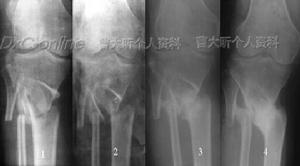

2、骨牽針復位:病程在1周內的誤診病例,局部腫脹明顯,手法復位成功的機會不大,可用克氏針作2-5掌骨頸部骨牽引48小時後,再進行手法復位,有可能將月骨推回原位。X線片證實復位後,按上述方法進行石膏固定。

手術復位4、月骨周圍脫位的治療與月骨脫位類似:先用手法牽引手指,然後將脫位的腕骨由背側向掌側推壓,很易復位,復位後處理同月骨脫位。伴有舟狀骨折的月骨的月骨周圍脫位,治療方法應按舟狀骨骨折處理。

5、新鮮月骨脫位,對1、2型脫位,應儘早手法整復。向遠側牽拉患手,腕關節背伸,再將月骨壓回原位。將腕關節在掌屈45℃位固定1周后再將腕關節放平固定2周。除去外固定後練習活動。對第3型脫位,因前後韌帶已斷裂,血運完全喪失,可能發生壞死,宜早行切除術。月狀骨周圍脫位,手法整復不困難,術後處理同前。

陳舊性月骨脫位。對1、2型脫位傷後3-4周者,手法復位,不易成功。應行切開復位。術後處理同前。術中如發現軟骨已有退行性變時,則應切除。固定數日後即可開始活動。對第3型脫位者,則應予以切除。